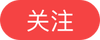

甲状旁腺是人体重要的内分泌腺之一,棕黄色形似大豆,分别位于左右两叶甲状腺背面(或埋在其中)中、下部。主要功能为分泌甲状旁腺激素(简称PTH),调节机体内钙、磷的代谢。

当甲状旁腺激素过度分泌和血钙过度升高时(原发性甲状旁腺亢进最为常见,多由甲状旁腺腺瘤,增生或腺癌所致), 便会导致引起全身代谢紊乱的疾病。早期仅仅表现为轻度骨质疏松、运动受限,疲劳便秘记忆力减退、精神异常等,后期进展为严重的骨折、骨骼变形,骨骼空洞等,走路困难,甚至生活不能自理;泌尿系小结石、尿毒症;而严重的高钙危象,可以导致严重的心率异常、昏迷,甚至可以导致患者死亡。严重影响患者生活质量甚至于生命危险。而且起病隐匿,非常难以早期发现。甲状腺就像一只美丽的大蝴蝶,而甲状旁腺亢进就是隐藏在“蝴蝶背后的危机”。